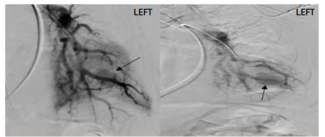

Rajat Datta, MD, DM; Vivek Singh Guleria, DM; G. Keshavamurthy, DM; K.J. Ratheesh, DM; Prashant Bharadwaj, DM

The authors present a case report where a deployed valve popped out due to underexpansion.